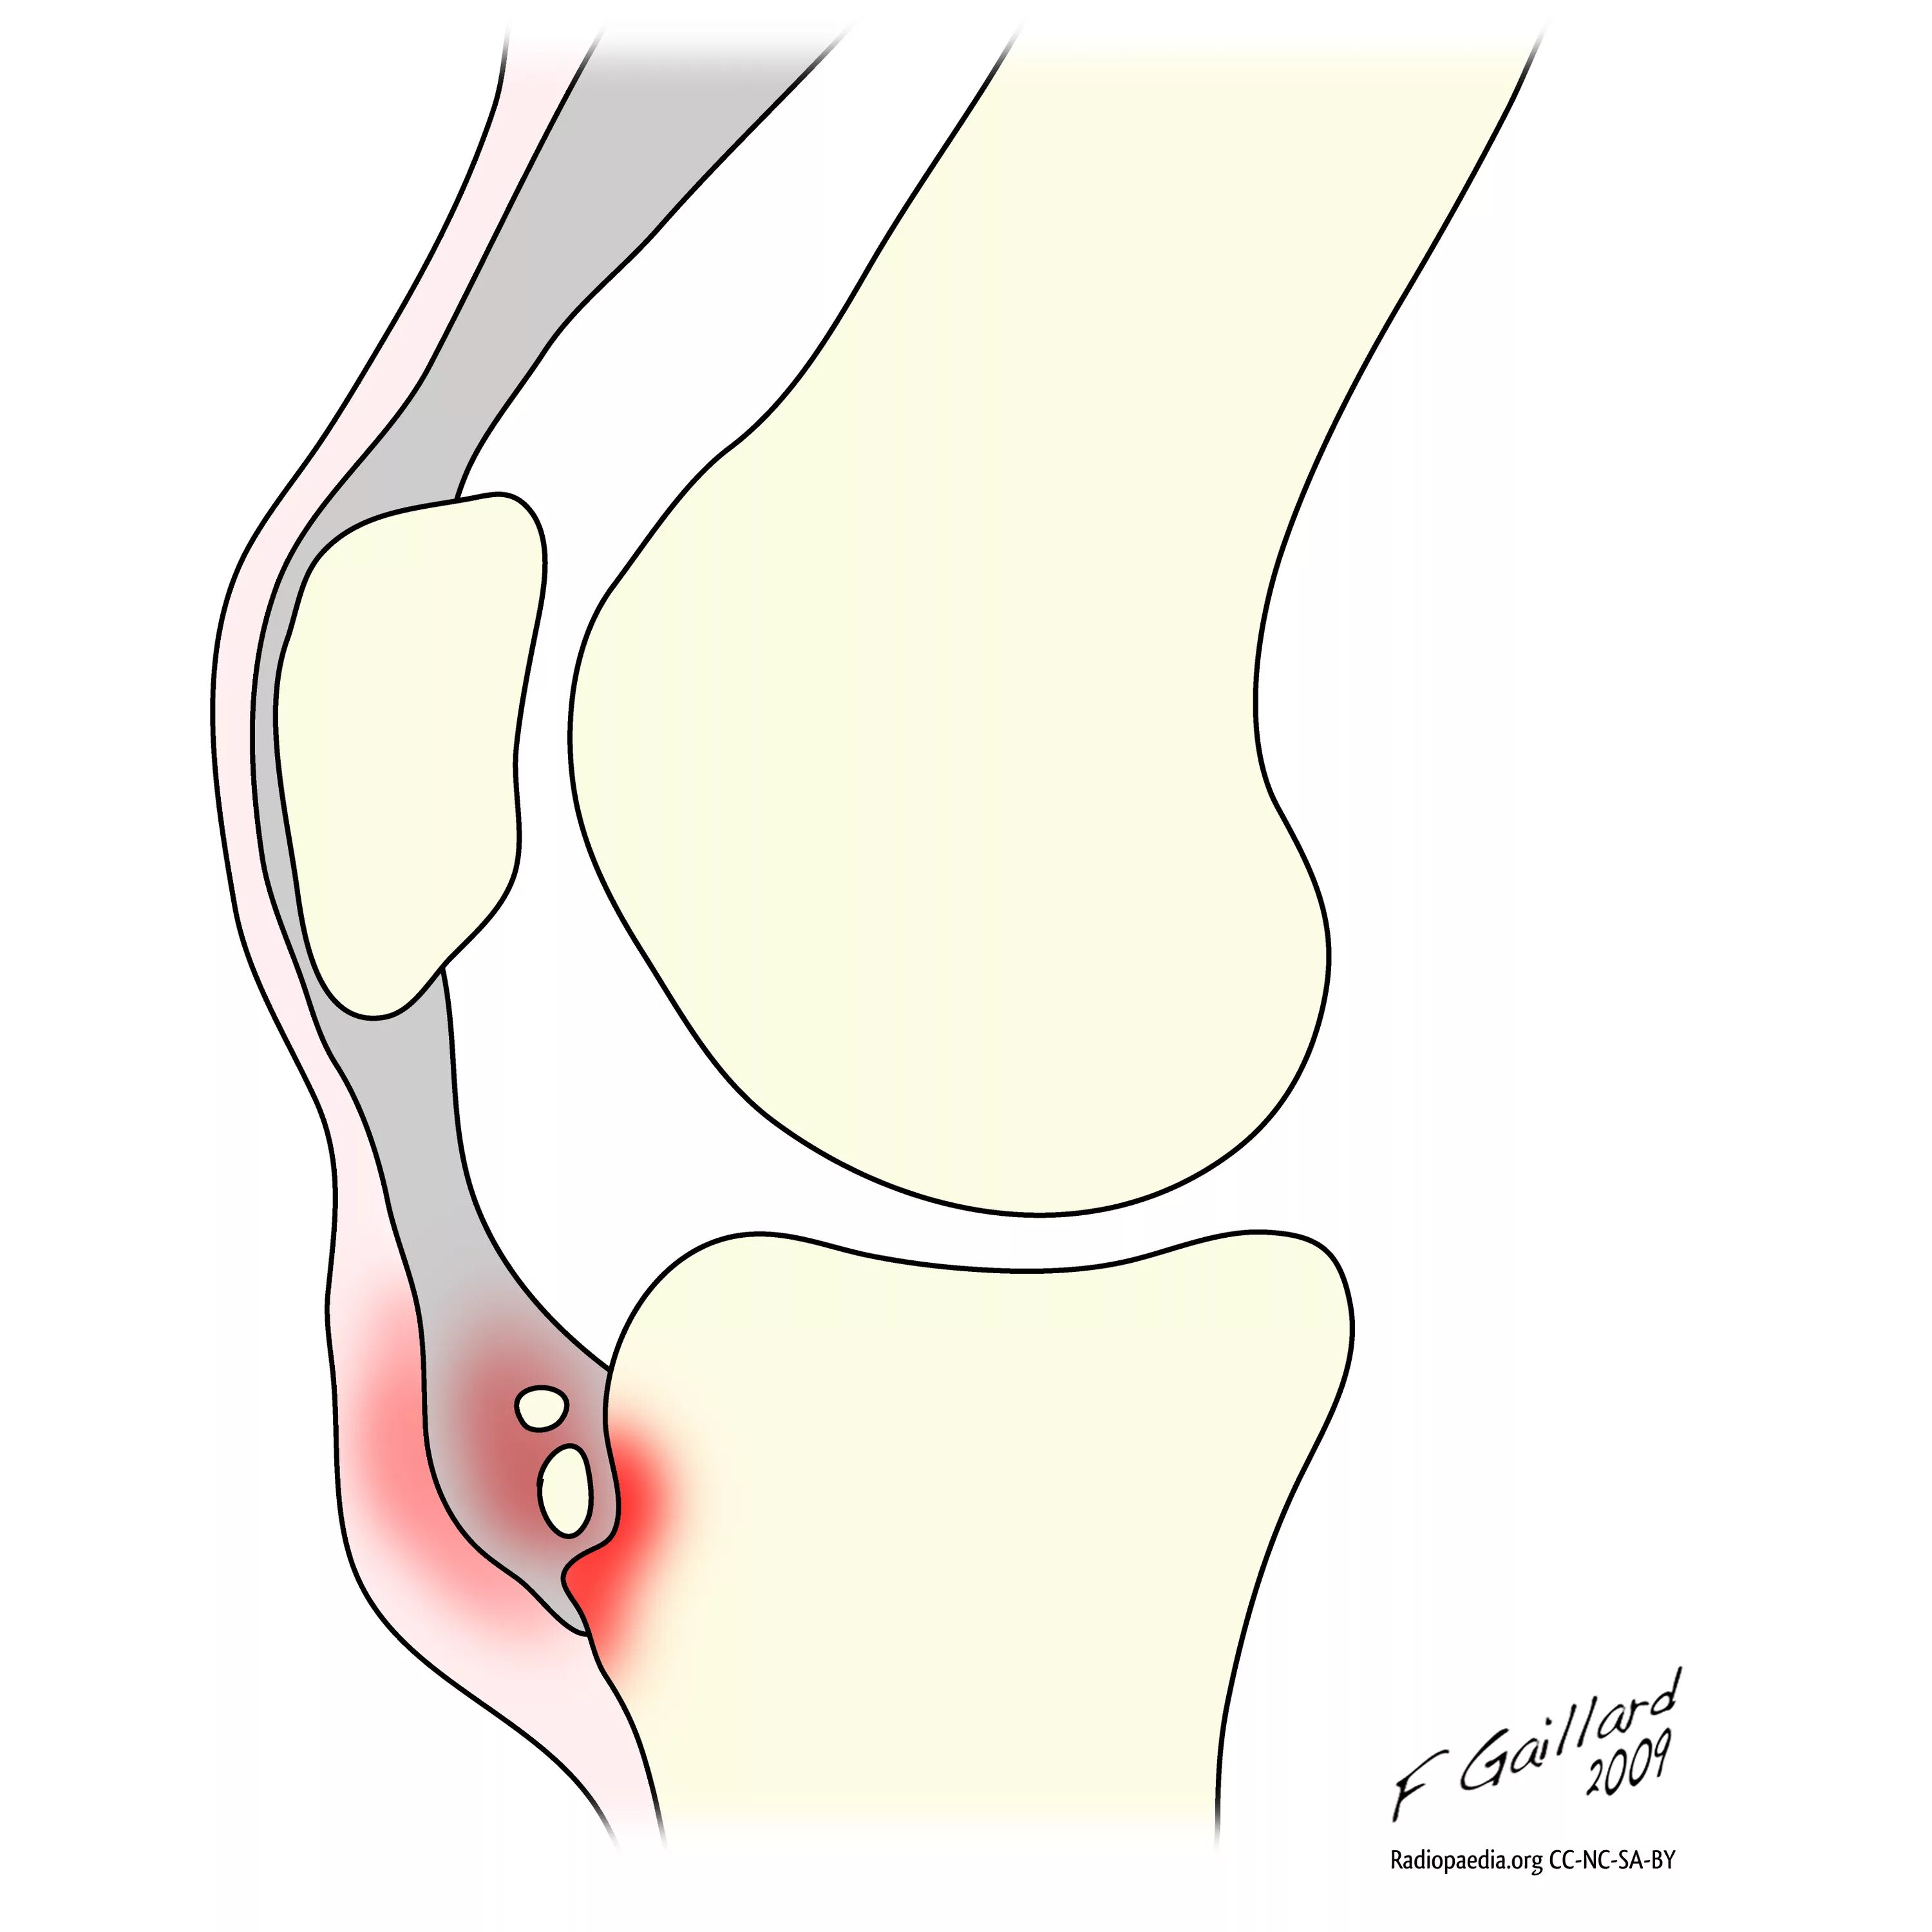

Синдром осгуда шляттера